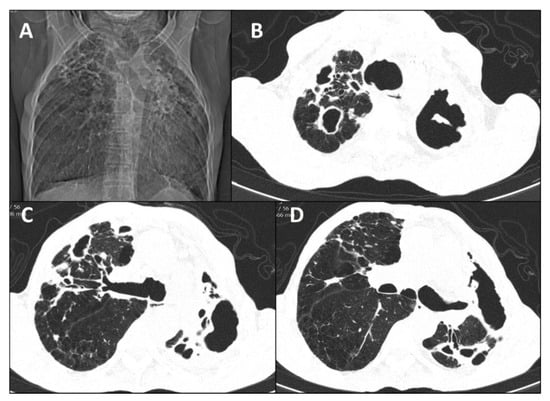

3.3. Radiological Patterns

| 1 (2018) | Male | 71 | None | Primary pulmonary | Lungs | Alcoholism COPD | No | Reticulonodular infiltrate; cavitation; fibrosis Unilateral/Multilobar | Sputum; BAL | ITZ; PSZ | Under treatment |

| 2 (2018) | Male | 63 | Contact with cat | Disseminated | Lungs, bone | Alcoholism COPD | No | Cavitation; fibrosis; hilar lymphadenopathy Unilateral/Unilobar | Sputum; BAL | ITZ; AmB; PSZ | Under treatment |